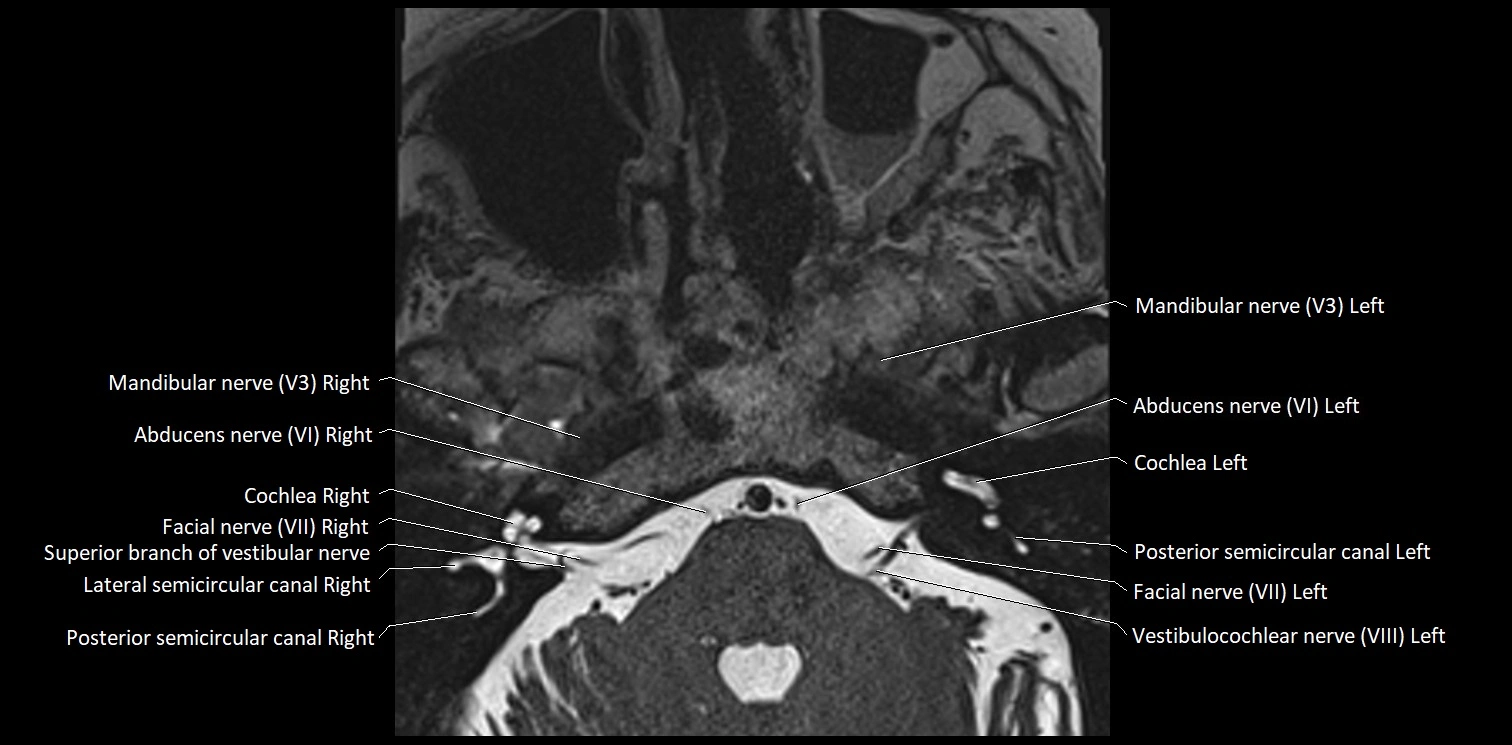

MRI Appearance

• The abducens nerve is a small, thin, linear structure

• Best visualized on high-resolution T2-weighted 3D MRI sequences (e.g., FIESTA or CISS)

• Seen as a hypointense (dark) line running from the brainstem at the pontomedullary junction, traversing the prepontine cistern, and entering Dorello’s canal under the petrosphenoidal ligament, then into the cavernous sinus, and finally the orbit

• May be challenging to visualize in standard MRI due to its small size

• Pathology may be inferred by absence, displacement, or enhancement of the nerve

MRI images

image